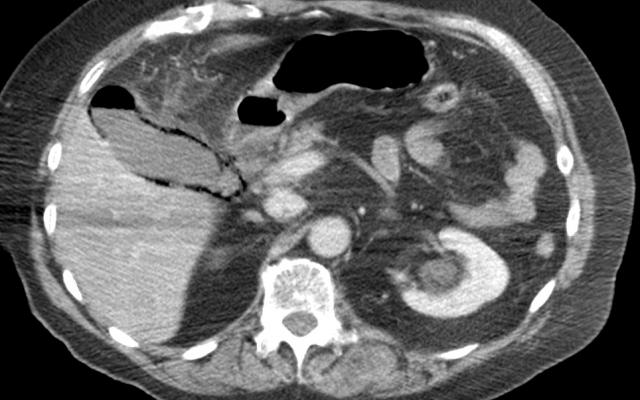

Dit artikel is alleen beschikbaar als PDF.Lees de PDF Artikelinformatie Online verschenen op 29 april 1955 Citeer dit artikel als Ned Tijdschr Geneeskd. 1955;99:1949 Heb je nog vragen na het lezen van dit artikel? Check onze AI-tool en verbaas je over de antwoorden. ASK NTVG Ook interessant Nieuws Plethora en numerus fixus Beeldquiz Een brakende oude man met buikpijn en koorts Beeldquiz Een brakende man met retrosternale pijn en dysfagie Meer gerelateerd … Reacties Login om een reactie te plaatsen